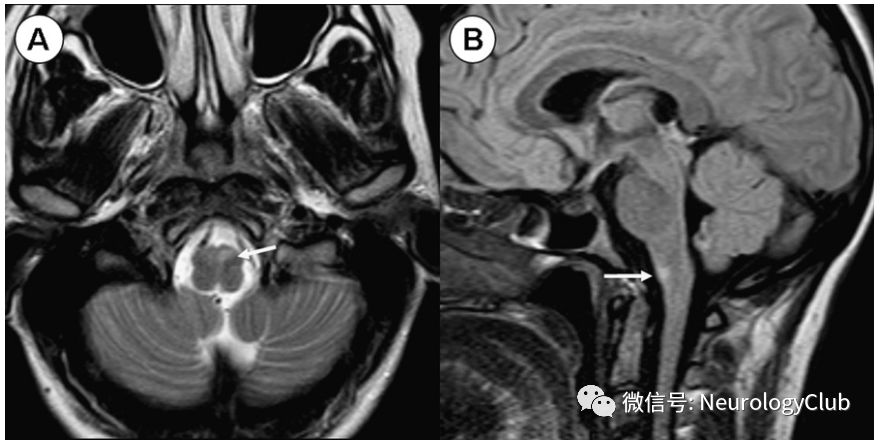

中脑背部梗死(图5)引起复视、垂直性凝视障碍和其他动眼综合征。此外,还可出现耳鸣、听觉过敏和听力丧失。

图5:中脑背侧梗死;62岁患者,表现为眩晕、复视、垂直性凝视麻痹;A:轴向t2加权像未显示任何异常。(B)轴向各向同性扩散加权图像。(C)ADC图显示左侧背部血管区域急性缺血性梗死的典型影像学特征